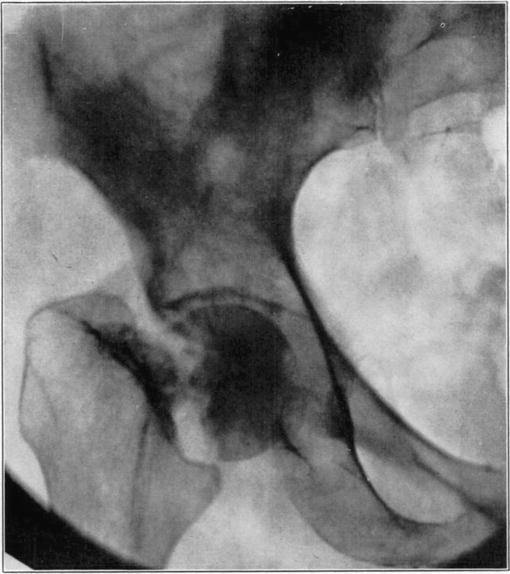

Necrosis of the proximal fragment in complete intracapsular fracture of the neck of the femur occurs in a not inconsiderable percentage of the cases. Santos [7] has recently completed a detailed study which has thrown light on many aspects of the condition. A summary of his report follows: Necrosis may occur in fractures at any age, and although relatively more frequent in older persons, it is often absent in them. This may sometimes be because of blood reaching it by way of vessels in the untorn periosteum. The vessels of the ligamentum teres may supply adequate blood to keep the head alive even in the aged.

Death of the proximal fragment predisposes to non-union, but union occurs in a considerable percentage of the cases with a dead head in which there is impaction of fragments or in which there is efficient reduction and fixation of fragments, the best results apparently being obtained from the closed abduction method of Whitman. At the end of the period of immobilization the distal living fragment usually shows roentgen-ray signs of reduced density due to atrophy of disuse, but the necrotic head which cannot atrophy casts practically as even and heavy a shadow as at the time of fracture. This usually makes it possible to diagnose necrosis roentgenologically at this stage.

If bony union occurs the head is gradually invaded by the ingrowth of tissue from the distal fragment and sometimes from the hypertrophied round ligament. The necrotic marrow is replaced by vascular connective tissue and eventually by bone marrow, but the necrotic bone is much more slowly absorbed and replaced by a variable amount of irregularly arranged living bone. The necrotic cartilage is slowly absorbed and replaced by fibrous tissue, fibro-cartilage, and to some extent eventually by new hyaline cartilage. If too much weight is borne on the head before it has been transformed into new bone, its weight-bearing portion may collapse with a resultant deformity and a poor functional result, but this may be averted by prolonged avoidance of weight-bearing. The functional stimulation which comes from motion of the limb without weight-bearing is sufficient to hasten transformation of the head.

Necrotic femoral head casting heavier shadow than surrounding atrophied living bone.

Roentgenogram of slice of excised head in Fig. 7, showing old necrotic bony trabeculae still undisturbed.